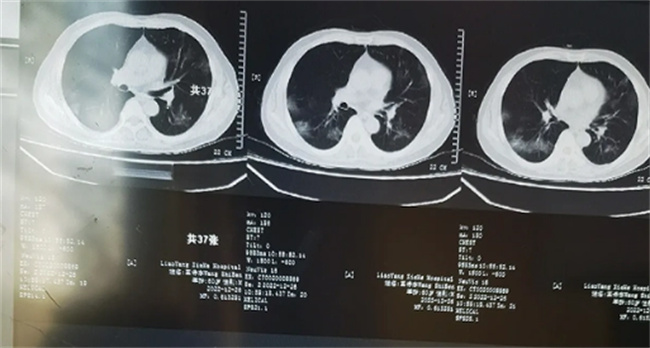

在拍摄X光片之后会发现肺部是黑色的,因为里面就会有着众多的气体,而这些气体很容易就会直接透过去,在经过拍摄之后会发现是黑色。但如果肺部有炎症出现渗出,等现象X光就不容易透过去,此时在拍摄完毕之后就会是一种白色。如果大部分的白色,这就会导致患者的正常呼吸,产生相应的影响,属于一种重症,需要尽快的接受治疗。

根据医生介绍,如果在确诊阳性之后的1~2个星期内出现一些异常的症状,建议不要忽视,应该及时到医院拍摄CT。许多的患者在确诊阳性之后,就会有浑身疼痛,高烧咳嗽等症状,但这些症状基本上在一个星期左右就会逐渐的消失。可是也有一些人会比较特殊,在转阴之后反而会出现咳嗽,持续低烧,呼吸困难,还有乏力等现象,建议不要过于的忽视,可以到医院去做一个检查。很可能是引发肺炎,此时随时都有可能会危及到性命。

老年人要预防“沉默性低氧”

最近一段时间有无数的老人都是因为沉默性低氧而离开人世,老年人一般对于缺氧的反应比较迟钝,可能没有感觉到自己有呼吸困难或者是胸闷等症状。这些老人在发现问题然后送到医院的时候,肺部基本上已经出现大面积的白色,这个时候早就已经为时已晚,错过了最佳的治疗时间。